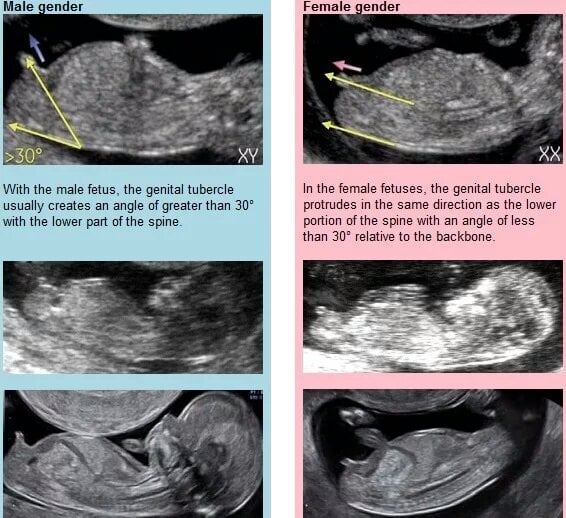

AnonymBruker Skrevet 21. januar 2023 #11 Skrevet 21. januar 2023 Jente! nuben viser rett/ned. Ikke opp som på gutt. Anonymkode: c2eef...41b

AnonymBruker Skrevet 21. januar 2023 #19 Skrevet 21. januar 2023 Hvilken uke er ultralyden tatt? Jeg syntes fosteret så ut som det var eldre enn perioden hvor en kan bruke nub-teorien, men det er bare ut i fra de ultralydbildene jeg har av mine barn. Jeg er ikke i nærheten av fagperson, så det blir egentlig bare vill gjetting. Jeg klarte å se nub'en på bildene av mine i uke 12 fordi han som utførte ultralyden viste meg hva som var den. På dette bildet klarer jeg i hvert fall ikke å se noen "gutte-nub". Altså noe som ser ut til å ha over 30 graders vinkel fra ryggraden. Dermed gjetter jeg jente. Men jeg vet ikke om noe av det jeg ser der er en nub da. Alt jeg ser av streker har i hvert fall under 30 graders vinkel i forhold til hverandre. Det som står rett opp der, ser ikke ut som noen nub. Jeg gjetter navlestreng eller et bein. Anonymkode: acd22...99f